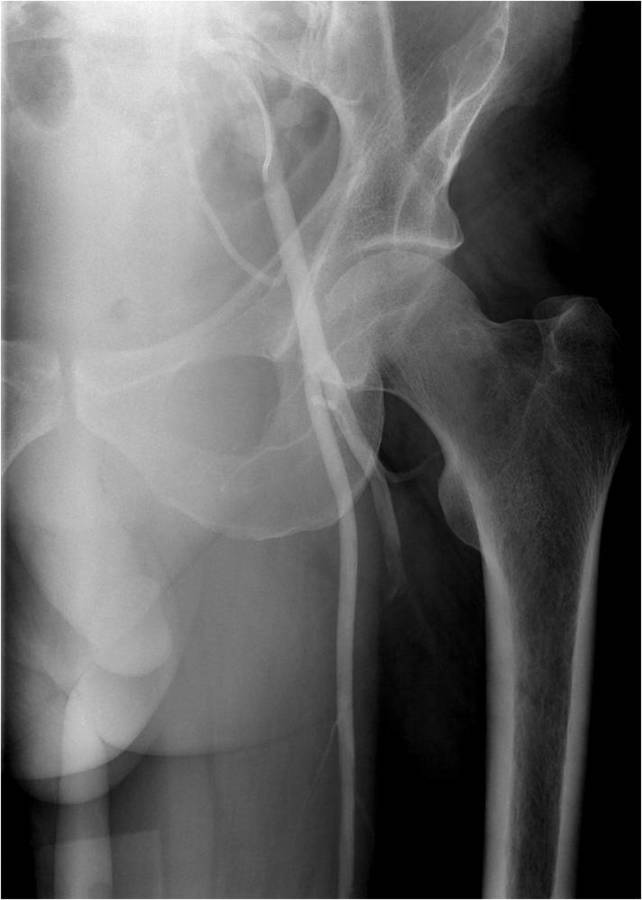

Gallery of Unlabled Radiographs from Lecture (Dr. French) - 2020

Click a thumbnail to enter the gallery display. Click the file name link at the bottom left of the gallery display to view the image at high resolution.